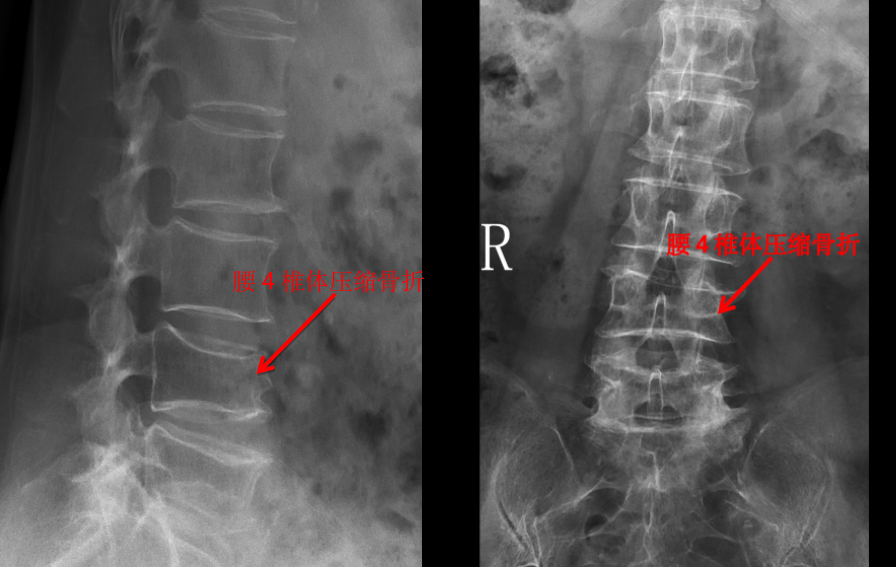

X 線檢查

我們管 X 線檢查叫 X 光片、照相或拍片。在 X 光片里,我們能看到脊柱有沒(méi)有骨折,有沒(méi)有骨質(zhì)破壞,有沒(méi)有脊柱側(cè)彎、有沒(méi)有骨質(zhì)增生等。一些有經(jīng)驗(yàn)的大夫,可以通過(guò)椎間隙高度的丟失判斷椎間盤(pán)的退變程度。

但是對(duì)于大部分軟組織病變?nèi)缱甸g盤(pán)、椎管內(nèi)神經(jīng)、有沒(méi)有占位性病變等卻無(wú)能為力。如果患者有壓縮骨折,X 光片也無(wú)法判斷是新鮮骨折還是陳舊骨折,這樣也就無(wú)法定制下一步診療計(jì)劃。

所以,X 光片的優(yōu)點(diǎn)是廉價(jià)、檢查快捷,缺點(diǎn)是對(duì)人體有輻射,組織顯像有限,只能看骨頭,不能看軟組織。

一般來(lái)說(shuō),X 光片在脊柱外科里,屬于一種基礎(chǔ)檢查或篩查,對(duì)絕大多數(shù)腰背痛的病人都適用。

前面提到的腰椎壓縮骨折,X 光片可以看出楔形變,但無(wú)法判斷新鮮骨折還是陳舊骨折,進(jìn)一步完善腰椎 MRI 才能明確診斷,做出下一步治療計(jì)劃。